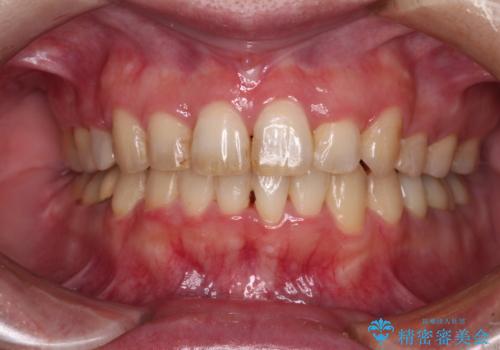

[ メタルフリー治療 ] 金属のない口腔内にしたい

![[ メタルフリー治療 ] 金属のない口腔内にしたいの症例 治療後](https://seimitsushinbi.jp/wp/wp-content/uploads/2021/09/7dd01ef5eeb5bcef896adc1f4413dba9-500x350.jpg?v=1632299935)